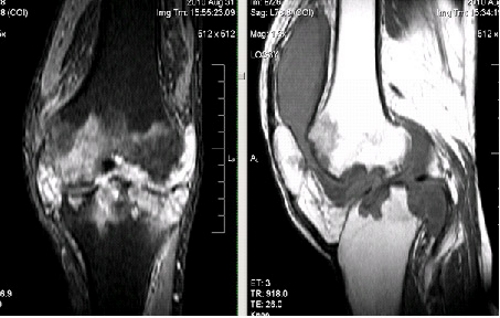

- рентгенографические исследования;

- ультразвуковое исследование (УЗИ);

- компьютерная томография (КТ);

- магнитно-резонансная томография (МРТ).